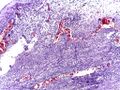

Even for clinically certain appendicitis, routine histopathology examination of appendectomy specimens is of value for identifying unsuspected pathologies requiring further postoperative management.[69] Notably, appendix cancer is found incidentally in about 1% of appendectomy specimens.[70]

Pathology diagnosis of appendicitis can be made by detecting a neutrophilic infiltrate of the muscularis propria.

Periappendicitis (inflammation of tissues around the appendix) is often found in conjunction with other abdominal pathology.[71]

Micrograph of appendicitis and periappendicitis. H&E stain

Micrograph of appendicitis showing neutrophils in the muscularis propria. H&E stain

Acute suppurative appendicitis with perforation (at right). H&E stain